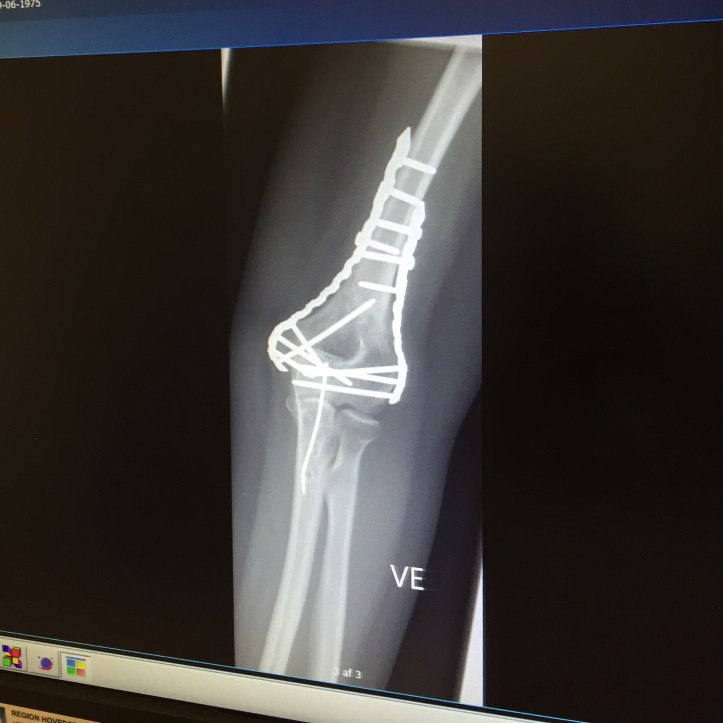

For those of you who are keeping count and are possibly still interested in the on-going saga of my smashed and rebuilt elbow, I am having a third and final round of surgery in March. This time it is to remove the final section of metal in the top part of my arm as the metal is resting on my ulnar nerve. I find myself talking to people expecting them to have the same level of anatomical knowledge that I now have about arms, bones and nerves and funnily enough they don’t. For many people they are surprised that I am still suffering and recovering from my injury over twelve months after the accident.

This time it has been a speedy process getting an appointment for the operation. I saw my GP on a Thursday who agreed to send the referral immediately for me. By Monday I had an appointment in my e-Boks for a week later. At that appointment, following an x ray, I had a fast diagnosis and a date in the calendar for the operation. I could have gone sooner but we have a break away booked for the winter holiday so it was best after that. I even saw the actual surgeon who would work on it and I ticked the consultation with the anesthesiologist off in the same visit.